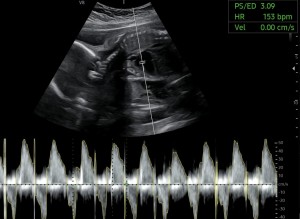

중기[13주~27주]

24주 입체초음파 찍고왔어요!

닉네임_유*은_3

2025-09-11

10

4